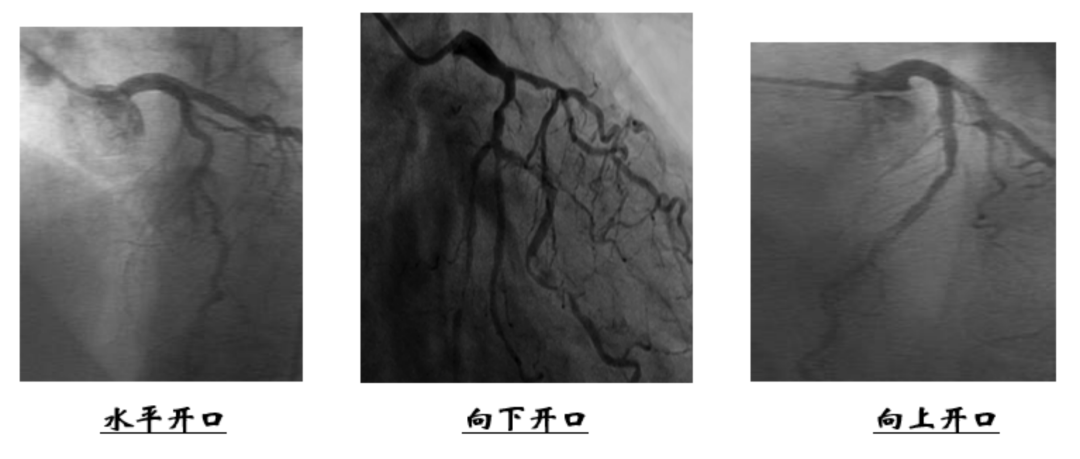

左冠指引导管选择需要考虑左主干开口的基本形态(如3),JACC 2010《首届国际经桡临床实践调查》中经桡动脉左冠指引导管使用情况调研显示,常用的左冠指引导管有EBU(40%)、XB(26.3%)、Judkins Left(JL)(22.5%)等。左冠特殊情况下指引导管的选择要结合血管解剖与病变部位当遇上回旋支复杂病变、近段严重扭曲、严重钙化病变、复杂分叉病变、LAD或LCX远段病变或慢性完全闭塞病变时,需要增大指引导管型号;当遇上LM较短、双开口靶血管为LAD、LM开口或干段病变、LAD开口支架或无名动脉严重迂曲时,需要减小指引导管型号。此外,由于经桡动脉入路的进入角度和经股动脉入路不同,相同指引导管能提供的支撑力较股动脉入路低。研究显示,JL经股支撑力比经桡支撑力强60%,而EBU、XB经股支撑力比EBU经桡支撑力仅强8%。桡动脉时代,EBU、XB替代JL成为左冠主流指引导管。

右冠脉解剖变异较大,因此右冠脉较左冠脉难以到达,而且右冠脉开口病变多见,如导管操作不当可直接造成开口的撕裂,因此选择导引导管应更加慎重。JACC 2010《首届国际经桡临床实践调查》经桡RCA指引导管使用情况调研显示,最常用的右冠指引导管为Judkins Right(JR)(70.2%)。右冠指引导管的选择需要考虑的解剖因素有:主动脉的宽度、上肢动脉迂曲程度、起始段走行和右冠开口位置等。图5为指引导管头部形状选择建议。

JR指引导管的特点是操作简单、安全性高,适用于开口正常的常规简单病变,但支撑力较弱,临床上根据主动脉宽度选择JR导管(图6)。对于高位RCA、向上开口、同轴性不好、位置异常、主动脉显著增宽、头臂干/无名动脉迂曲等的患者,JR导管难以提供良好的支撑。

JL指引导管是需要强支撑RCA操作的另一个选择。JL指引导管用于RCA操作的优点是可以通过底部及对侧提供强支撑,即指引导管第一弯抵在窦底部、第二弯贴合对侧主动脉壁上,形成“倒钩”型,提供强力支撑。JL3.5指引导管是最常用于RCA脉操作的JL指引导管。对于RCA向上/水平发出,JL更易与RCA同轴;RCA开口偏低且向下发出或RCA起始段细小/开口病变不建议使用JL指引导管。在病变类型上,JL指引导管适用于需要中强支撑的分叉、钙化、迂曲成角、弥漫长病变及CTO病变,对于简单病变,应尽量选用JR/SAL,更加安全易用。JL 指引导管RCA初步到位操作根据情况可考虑使用带侧孔型号或自制侧孔,防止嵌顿;置入导管时用J型导丝协助塑形,一般导管先进入左窦;然后将导管提到右窦上方,再将其头端送至右窦底;注意不要直接将导管从左窦向右窦旋转,否则操作困难,有时甚至会突然跳入RCA,导致损伤;最后沿窦底缓慢旋转导管,寻找RCA开口并插入。JL3.5指引导管到位RCA后有时插入过深,易导致压力嵌顿,甚至引起冠脉夹层;或者“悬”在右冠状动脉口部,两种情况均无法获得安全强力的支撑。这时需要送入一根通用导丝(如BMW导丝),送至冠状动脉远端,同时使导丝远端反折成圈,然后用力前送导丝,使导管头端稍稍离开RCA口部,在保持导丝张力的情况下,左手前送导管,使导管第一弯下“坐”至窦底,形成“倒钩”型,获得强支撑。RCA病变使用JL3.5指引导管的注意事项:回撤器械时可能导致导管深插损伤冠脉,建议先将导管回撤“悬”在冠脉口部,再回撤器械。

不同的开口位置决定不同的指引导管,因此需通过导管造影技术仔细探寻冠脉开口位置。RCA开口于右窦偏前偏上,起源位置比较高,一般需要使用AL等导管头朝前下插入;RCA开口于左窦偏前游离壁,导管很难稳定,且无法同轴。右冠开口偏前或偏后时,一般选择C型指引导管,如SAL、MAC、AL等。左主干开口严重狭窄应选择带侧孔,硬导丝辅助打开使指引导管并不直接到位而是位于开口下方,工作导丝到位后再调整指引导管。